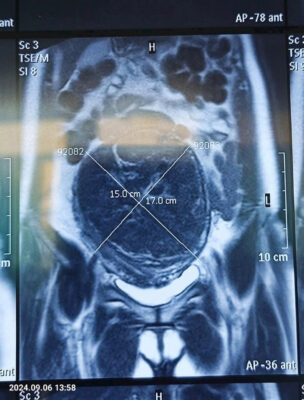

PHẪU THUẬT ĐIỀU TRỊ U XƠ TỬ CUNG KÍCH THƯỚC LỚN

🧑‍⚕️U xơ tử cung là khối u lành tính ở cơ tử cung, thường gặp ở phụ nữ tuổi từ 35-50 tuổi. Bệnh tiến triển từ từ, diễn biến lâm sàng đa dạng. Nếu u nhỏ, thường không gây triệu chứng đáng kể, sau 1 đến 2 lần có thai hoặc đến mãn kinh u có thể ngừng phát triển. Tuy nhiên nếu khối u quá lớn có thể gây đái rắt, đái khó, chèn ép niệu quản, ứ nước thận, chèn ép trực tràng gây táo bón trường diễn… U xơ tử cung có thể gây ra nhiều biến chứng về sản- phụ khoa như rong kinh, chậm có thai, vô sinh, làm tăng nguy cơ sẩy thai, nhiễm trùng hậu sản.

🧑‍⚕️Có nhiều phương pháp điều trị UXTC áp dụng cho từng trường hợp cụ thể. Có 2 nhóm phương pháp điều trị chính là điều trị bảo tồn và phẫu thuật. Trong đó phẫu thuật bóc nhân xơ, cắt tử cung bán phần hoặc toàn phần là kỹ thuật được áp dụng rộng rãi trong các bệnh viện. Chỉ định phẫu thuật cho các trường hợp UXTC kích thước lớn, gây cảm giác khó chịu cho người bệnh; UXTC gây biến chứng nặng như xuất huyết tử cung bất thường dẫn đến thiếu máu, sẩy thai liên tiếp…, UXTC điều trị nội khoa thất bại.